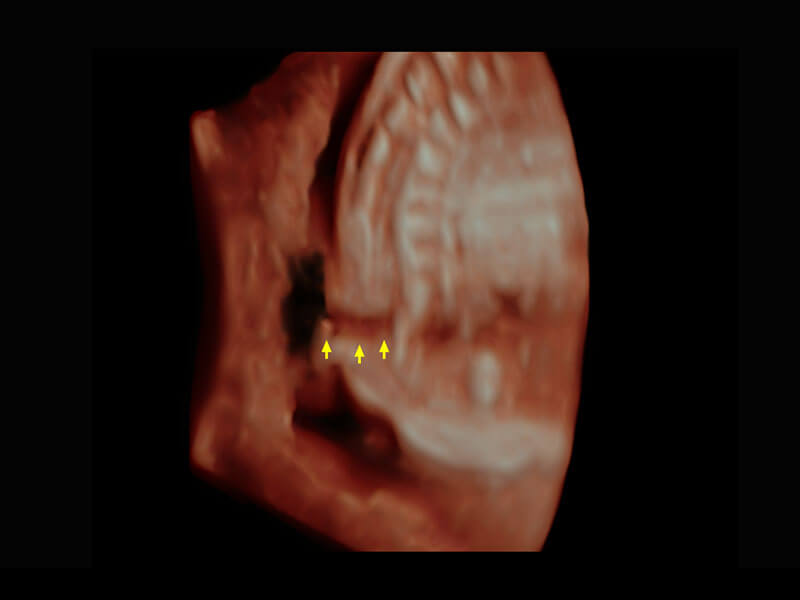

P60搭載一系列胎兒心臟成像技術(shù),實現(xiàn)精細的胎兒心臟評估。

胎心容積成像